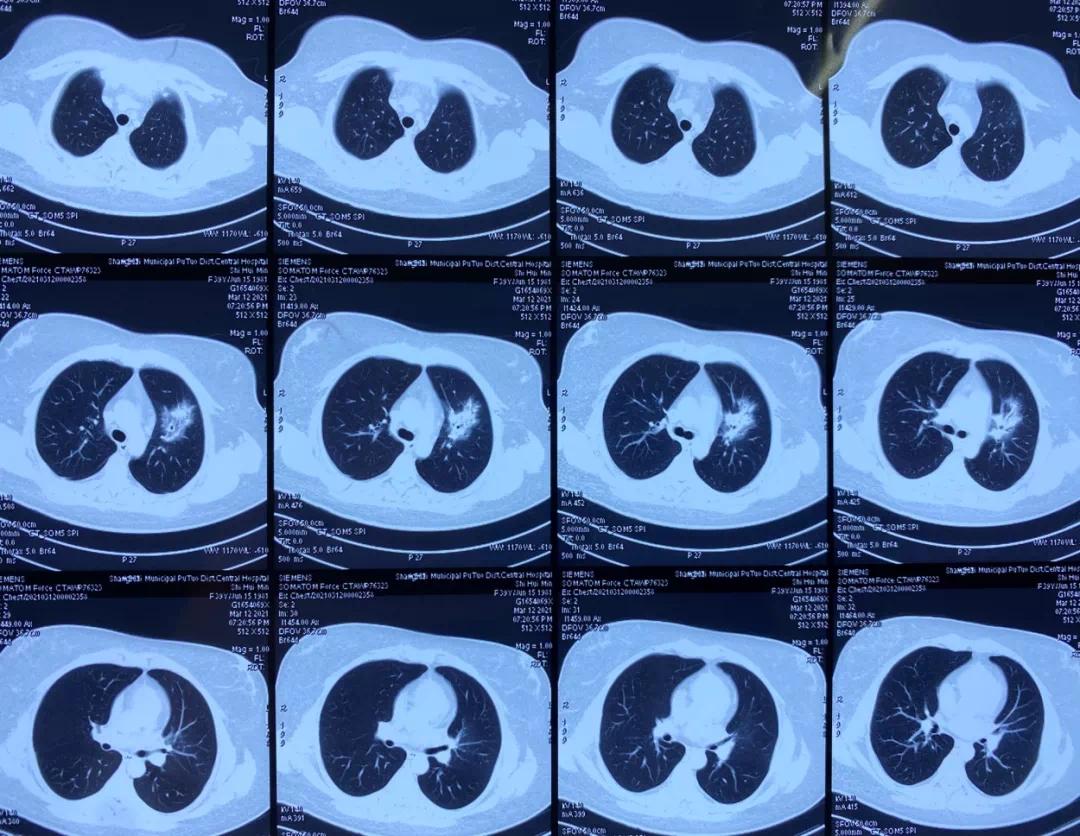

医生用左氧氟沙星联合头孢曲松抗感染治疗3天,于小姐体温仍持续39-40℃,并出现咳嗽、咳少量白痰、胸闷,且症状逐渐加重。查胸部CT,医生的诊断是“左肺上叶及右肺下叶炎症”。

△于小姐胸部CT诊断为“左肺上叶及右肺下叶炎症”图片来自“上海长征医院”微信公众号(下同)